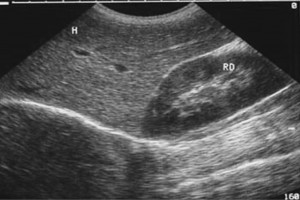

Diplomados en Ultrasonografía